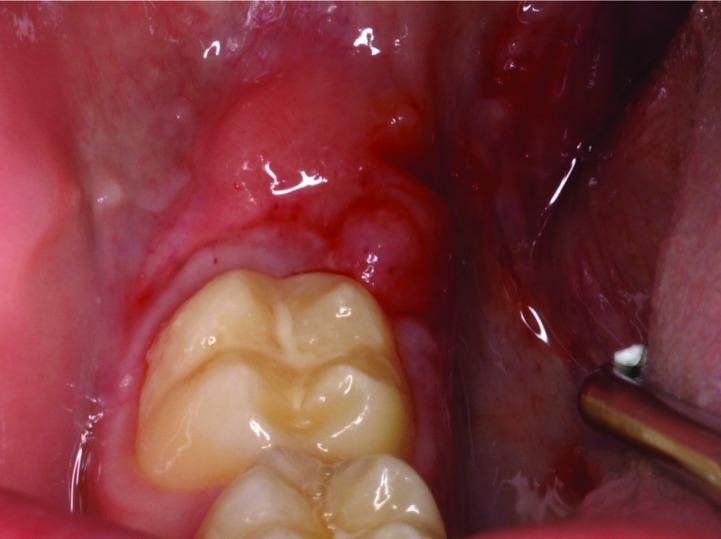

Orofacial granulomatosis is defined by permanent or recurrent swelling of orofacial tissues with different multiform and multifocal clinical patterns. An 11-year old boy presented with a 2-month history of mucosa enlargement. Intraoral examination revealed an erythematous, polylobulated, exophytic lesion with a smooth surface located in retromolar mucosa, non-tender and non-infiltratated to palpation. The diagnosis was inflammatory lesion compatible with pyogenic granuloma and laser excision was decided. Haematological parameters were within normal range, as well as chest Xrays. These findings lead to a diagnosis of non-symptomatic orofacial granulomatosis, whose early diagnosis can minimize the impact of systemic-related disorders, like Chron's disease. Key words:Laser, orofacial granulomatosis, childhood, oral lesions, diagnosis.

口面部肉芽肿病的定义是口面部组织出现持续性或复发性肿胀,具有多种不同形态和多灶性的临床模式。一名11岁男孩有2个月的黏膜肿大病史。口腔检查发现一个位于磨牙后黏膜的、表面光滑的、多叶状、外生性的红斑性病变,触诊时无压痛且无浸润。诊断为与化脓性肉芽肿相符的炎性病变,并决定进行激光切除。血液学参数以及胸部X光片均在正常范围内。这些发现导致诊断为无症状性口面部肉芽肿病,其早期诊断可将克罗恩病等全身性相关疾病的影响降至最低。关键词:激光、口面部肉芽肿病、儿童、口腔病变、诊断